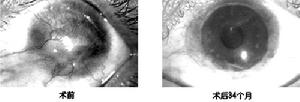

⑵角膜移植:鹼燒傷後的角膜移植具有很大危險性,併發症多。傷口癒合不良、移植片感染、排斥反應後移植片自溶、遷延性葡萄膜炎及眼球萎縮等一系列嚴重的併發症都可能發生。但在燒傷早期,如角膜潰瘍有穿孔趨勢,可立即作治療性板層角膜移植。在燒傷後,變薄的角膜伴密集的新生血管或變厚伴有大量增生瘢痕及肉樣血管翳,穿透性角膜移植不能成功。須待1年以後炎症反應完全靜脈,對新生血管,用β射線照射,總量400~420γ;或氬雷射擊射使之萎縮。照射半年後,先作改善基地的板層角膜移植術,使角膜厚度趨於正常。在此基礎上待1年以後方可考慮小直徑的穿透角膜移植。若傷眼為僅有的單眼,更應慎重從事,在具備上述條件時,儘量作板層全形膜移植術。應採用新鮮角膜材料,保留上皮,用極細縫線,術後正確使用皮質類固醇及膠原酶抑制劑點眼,以期獲較發效果。